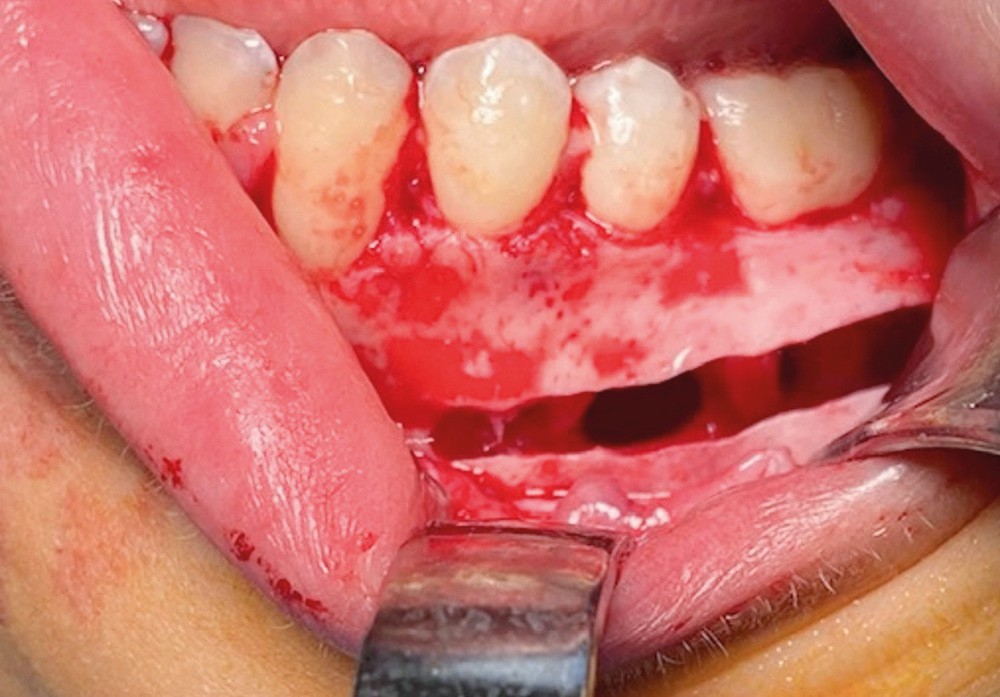

Le diagnostic est fait lors de l’intervention : la cavité est « vide », ne contenant aucune poche kystique (fig. 5).